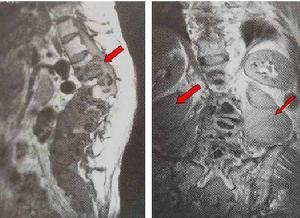

♥脊椎骨骨髓炎

脊椎骨骨髓炎在临床上也是十分常见的,其中半数患者为急性发病,其余半数为亚急性或慢性发病,患者以20-40岁青壮年为多见。男性约为女性的4倍。